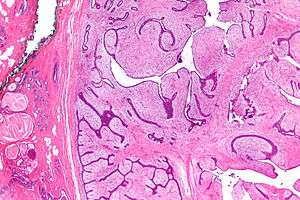

| Micrograph of a phyllodes tumor (right of image) with the characteristic long clefts and myxoid cellular stroma. Normal breast and fibrocystic change are also seen (left of image). H&E stain. | |

Phyllodes tumors are a fibroepithelial tumor composed of an epithelial and a cellular stromal component. They may be considered benign, borderline, or malignant depending on histologic features including stromal cellularity, infiltration at the tumor's edge, and mitotic activity.[1] All forms of phyllodes tumors are regarded as having malignant potential. A large series from the M.D. Anderson Cancer Centre reported the incidence of each as benign (58%), borderline (12%), and malignant (30%). Malignant phyllodes tumours behave like sarcomas and can develop blood-borne metastases. Approximately 10% of patients with phyllodes tumours develop distant metastases and this can go up to 20% in patients with histologically malignant tumours.[2] The commonest sites for distant metastases are the lung, bone, and abdominal viscera. Rare sites of metastasis like to parotid region have also been described.[3]